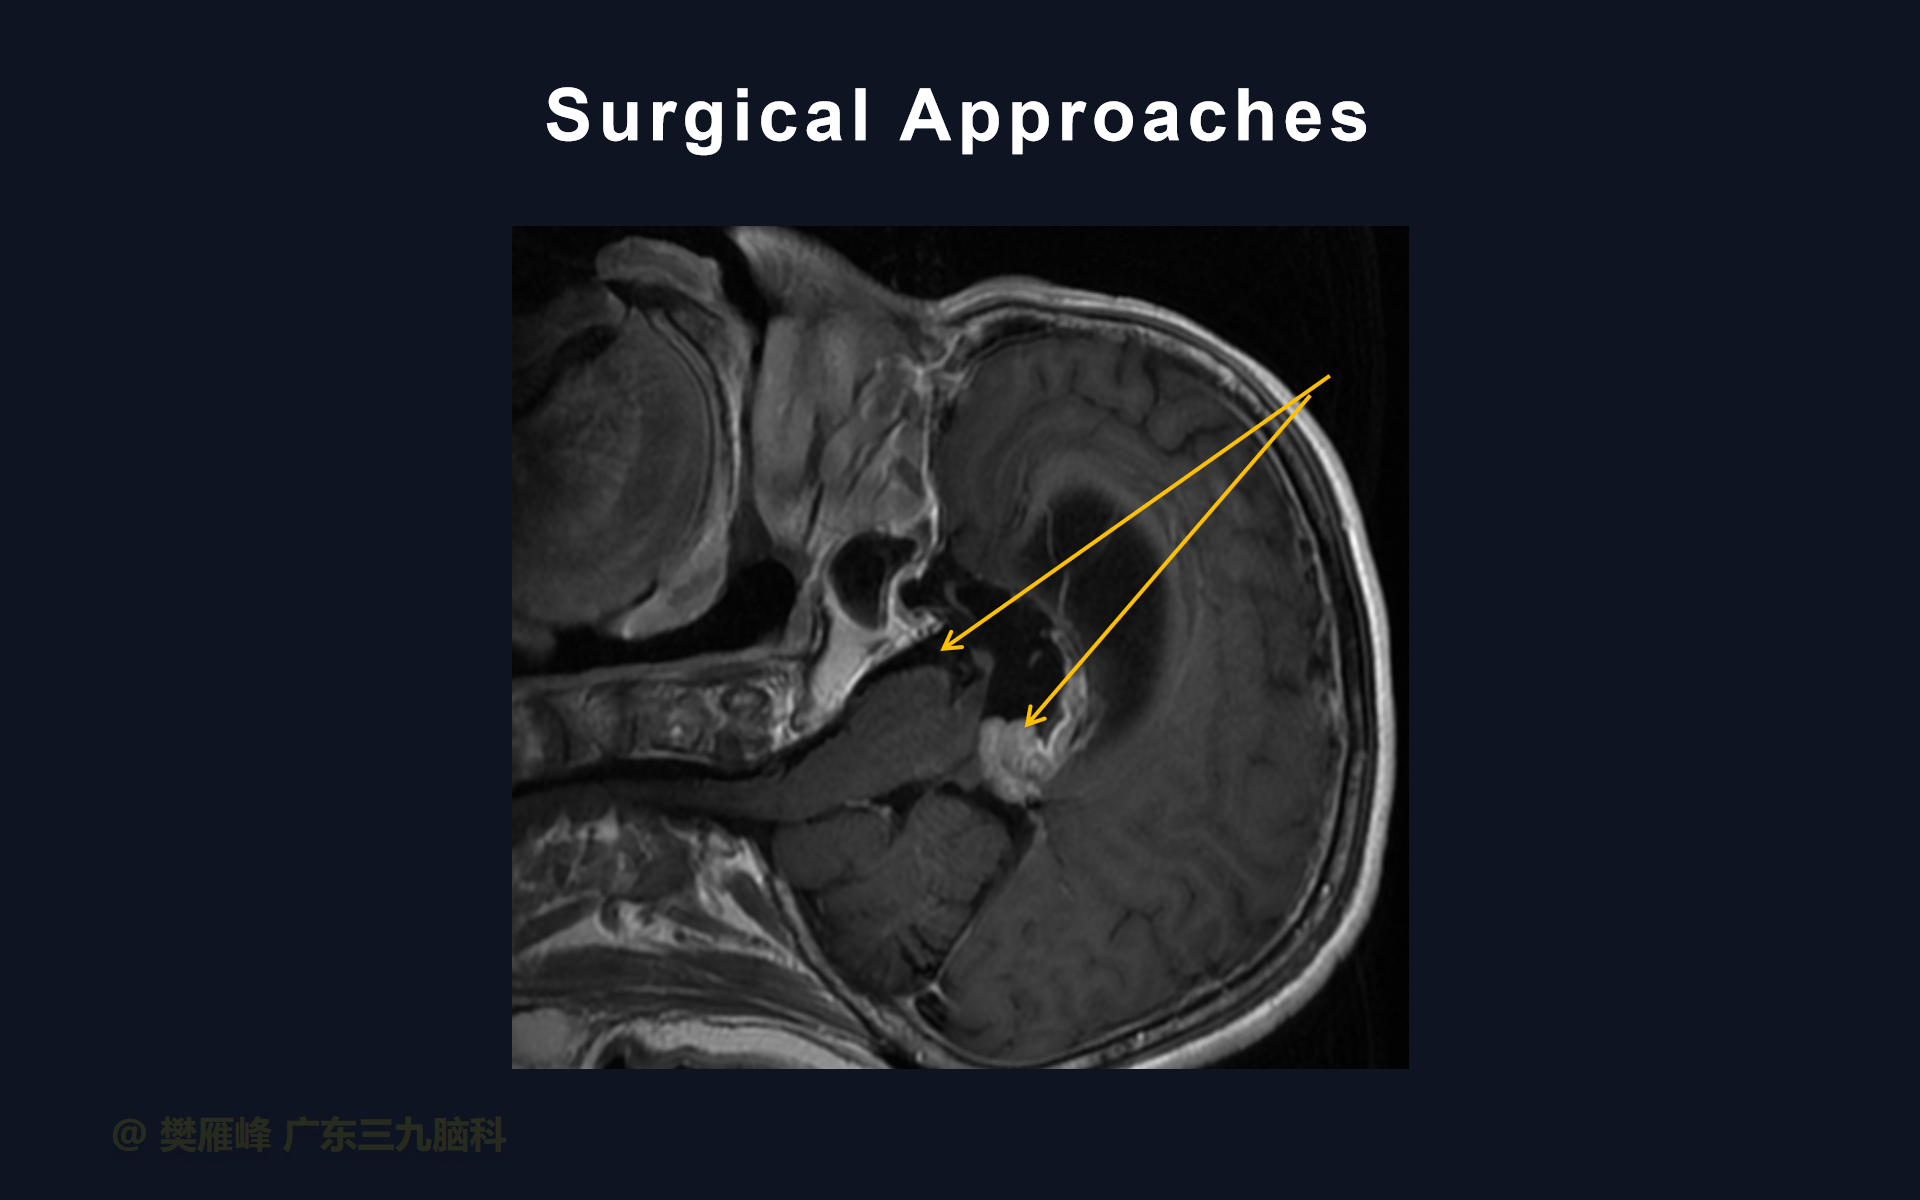

由于三脑室后部肿瘤患者的首发症状多为梗阻性脑积水引起,所以其治疗通常需先解决脑积水。对于非生殖细胞肿瘤,终极治疗手段为手术切除,应尽可能全切。但是,仅根据影像学和实验室检查往往难以在术前确定诊断。所以,组织病理学检查可帮助我们判断肿瘤是否需要全切,而对于那些不需要全切的肿瘤则可以避免积极手术带来的风险。

对于症状性脑积水,内镜下三脑室底造瘘优于脑室腹腔分流,可避免脑室腹腔分流引起的肿瘤细胞腹腔种植转移。然而,对于轻度或无症状的脑积水可不做特殊处理,因为肿瘤切除后脑积水一般自动解除。

第三脑室底造瘘时可同时行内镜下活检,这样,一次手术可处理脑积水获得病理诊断。

第三脑室后部肿瘤切除术前行ETV不仅有利于控制急性HCP,而且可以防止术后继发HCP的发生和最大限度地减少术后早期并发症。

在这个二维手术视频中,展示了2例神经内镜下三脑室底造瘘+活检治疗三脑室后部肿瘤的方法。患者均为三脑室后部病变导致的梗阻性脑积水,病理结果1例为生殖细胞瘤,1例为淋巴瘤,在经过术后的放化疗病情均得到控制,生活质量满意。我们展示了安全的病变活检和第三脑室造瘘的技术要点,以最大限度减少术后继发脑积水和早期并发症。